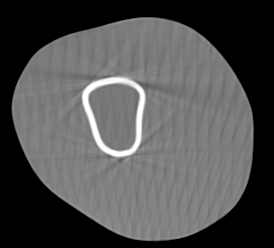

Involuntary subject motion is the main source of artifacts in weight-bearing cone-beam CT of the knee. To achieve image quality for clinical diagnosis, the motion needs to be compensated. We propose to use inertial measurement units (IMUs) attached to the leg for motion estimation. We perform a simulation study using real motion recorded with an optical tracking system. Three IMU-based correction approaches are evaluated, namely rigid motion correction, non-rigid 2D projection deformation and non-rigid 3D dynamic reconstruction. We present an initialization process based on the system geometry. With an IMU noise simulation, we investigate the applicability of the proposed methods in real applications. All proposed IMU-based approaches correct motion at least as good as a state-of-the-art marker-based approach. The structural similarity index and the root mean squared error between motion-free and motion corrected volumes are improved by 24-35% and 78-85%, respectively, compared with the uncorrected case. The noise analysis shows that the noise levels of commercially available IMUs need to be improved by a factor of $10^5$ which is currently only achieved by specialized hardware not robust enough for the application. The presented study confirms the feasibility of this novel approach and defines improvements necessary for a real application.